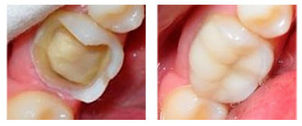

La reconstrucción dental es uno de los métodos más utilizados para recuperar y reparar los dientes. Estas técnicas están dentro del área específica que se llama Odontología Conservadora y Prostodoncia. Gracias a esto el paciente recupera la estética y funcionalidad de sus piezas dentales.

Hay diferentes maneras de reconstruir un diente, entre los que se pueden destacar: